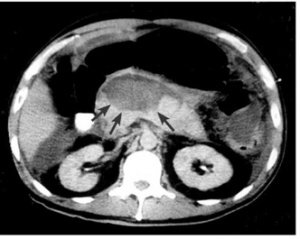

- טומוגרפיה ממוחשבת - הבדיקה השנייה בחשיבותה מאפשרת הדגמה של השאת ומיקומה (תצלום 18.9).

| תצלום 18.9: מימין -כיסית אמיתית בזנב הלבלב החצים מצביעים על גבולות הכיסית. משמאל - טומוגרפיה ממוחשבת מראה כיסית מדומה (פסוידוציסטה) מרכזית מדממת. | |